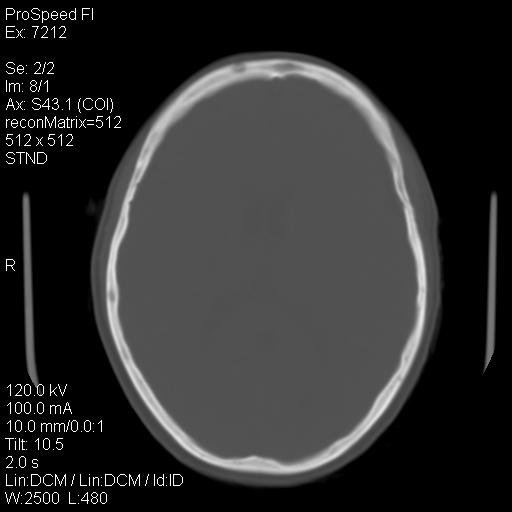

标题: CT18636:F 44Y,头痛三个月,左侧肢体麻木一周。临床诊断, [打印本页]

标题: CT18636:F 44Y,头痛三个月,左侧肢体麻木一周。临床诊断,

额顶骨多发穿凿样骨缺损区,不排除骨髓瘤等改变,进一步检查。

额顶骨多发穿凿样骨缺损区,不排除骨髓瘤或嗜酸性肉牙肿等改变,进一步检查。

1)右侧半卵圆中心腔隙性脑梗塞。2)考虑左侧额部慢性硬膜下血肿(或硬膜下积液)。3)颅骨骨髓瘤不排除;建议行进一步检查。